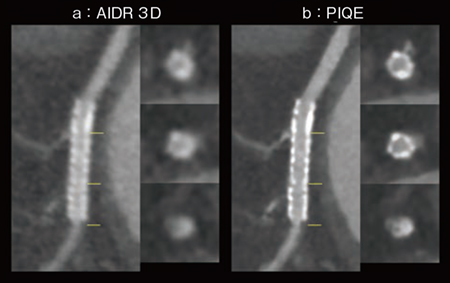

図2は,2.5mm径のステントが留置された,遠位部に中等度狭窄を呈した症例である。従来の「AIDR 3D」と比較して,PIQEでは空間分解能向上により,ステントからのブルーミングアーチファクトが低減されており,ステント内腔の視認性が向上している。また,ステント遠位部の狭窄や,内腔の低吸収領域を明瞭に描出している。ステント内腔の描出能向上により,3mm径以下のステント内再狭窄の診断能向上に期待できる。

図2 冠動脈ステント症例(2.5mm径)

a:AIDR 3D

b:PIQE

(画像ご提供:藤田医科大学病院様)